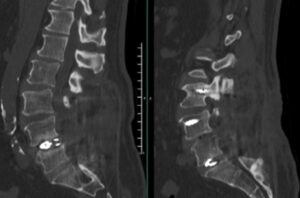

Dr. Paul Krafft uses stacked iFuse Bedrock Granite® in the SAI trajectories as well as in the S1 pedicle trajectory during a short construct revision case.